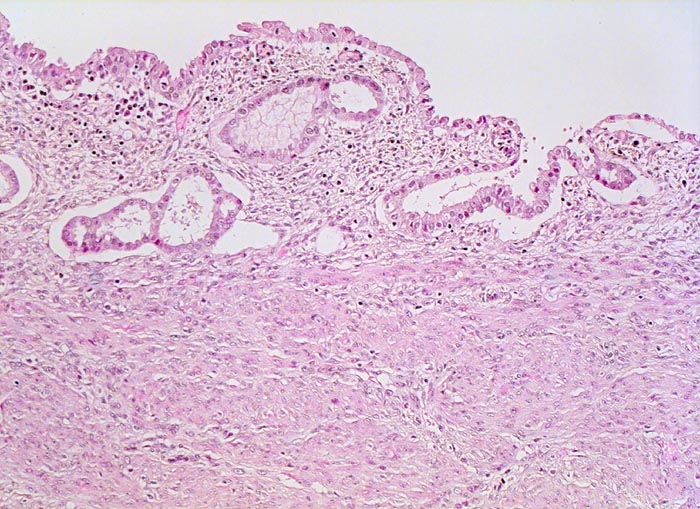

atrophes Endometrium

Das Endometrium besteht aus vereinzelten Drüsen mit atrophem Epithel und wenig zellarmem Stroma.

Exophytischer, in das Uteruscavum hineinragender, weicher fokal hämorrhagischer Tumor ausgehend von der Uterushinterwand. Das Tumorgewebe infiltriert die innere Hälfte des Endometriums.

Postmenopausale Blutung. Diagnose eines endometrioiden Adenokarzinoms in der Corpuskurettage. Daraufhin Hysterektomie, Adnexektomie und Lymphadenektomie.

Hoch und mässig differenzierte endometrioide Karzinome sind oftmals mit einer Hyperplasie des Endometriums assoziiert, wenig differenzierte Karzinome wie im vorliegenden Fall eher mit einem atrophen Endometrium.